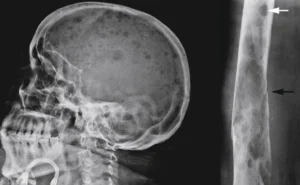

Varios exámenes y pruebas de investigación pueden utilizarse para ayudar a diagnosticar el mieloma múltiple:

3. Radiografías y otras pruebas de imagen.